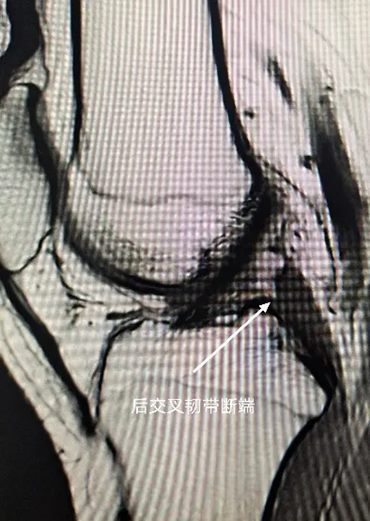

接诊的赵意华医师为他进行了详细检查,结合核磁共振结果,小王被明确诊断为:膝关节后交叉韧带断裂。这个诊断意味着维持膝关节前后稳定的一条重要“绳索”断了,对于他这样热爱运动的年轻人来说,必须通过手术重建韧带功能。